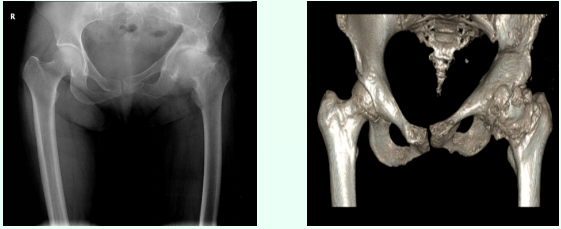

日前,我院应用3D打印技术辅助一名左侧创伤性股骨头坏死患者成功实施“左侧人工全髋关节置换”手术,解除患者二十余年的疼痛,助其恢复正常行走。